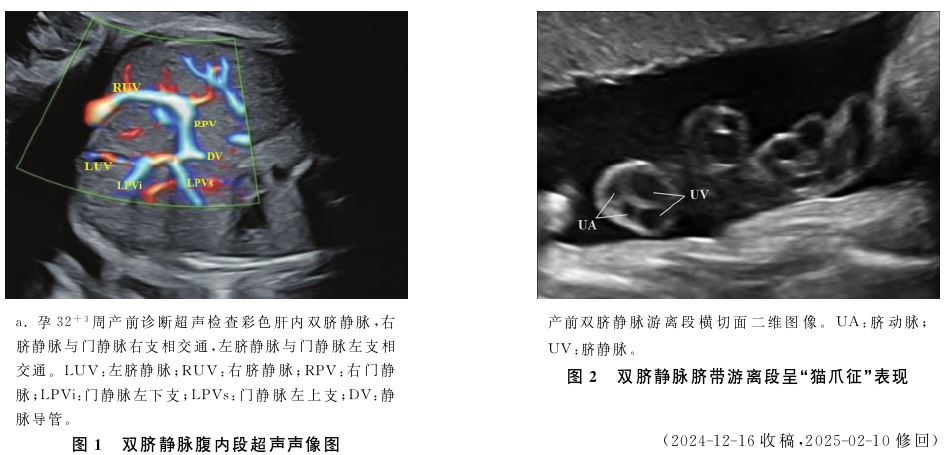

孕妇,29岁,自然受孕,孕1产0,单胎妊娠,产前常规查体。孕早期胎儿颈项透明层超声筛查未见明显异常,孕19周行无创胎儿染色体非整倍体检测提示低风险。孕24+0周于北京市海淀区妇幼保健院行产前超声筛查提示:胎盘前置状态,边缘性脐带入口。孕31+ 3周超声常规检查显示:胎儿肝内近脐带根部可见内径0.47cm的一分支血管与门静脉右支相交通,超声提示:胎儿肝内脐静脉异常血管分支,边缘型前置胎盘,边缘性脐带入口。孕32+3周产前诊断超声检查显示:胎儿腹部横切时可探及两支脐静脉自脐孔处发出,右脐静脉较左脐静脉粗大,二者各自发出门脉右支及左支并相连,胎儿胆囊位于右脐静脉左下方,超声提示:胎儿肝内左、右脐静脉并存,边缘型前置胎盘,边缘性脐带入口,见图1。孕37+3周因边缘型前置胎盘入院行子宫下段剖宫产术出生一男婴,体重3 240g,身长50cm,新生儿Apgar评分1、5、10min均为10分,术中出血约550mL。新生儿出生后1d超声提示:肝内见双矢状部,右侧矢状部粗大,呈优势,双矢状部分别连于左、右肝圆韧带,与产前超声诊断结果一致。胎盘娩出后病理送检示:胎儿脐带自蒂部至根部全程可见两粗、两细四根脐血管,诊断脐带血管变异———四血管脐带。

四血管脐带较为罕见,常伴先天性胃肠或心血管系统异常,可分为单脐静脉和双脐静脉,其中双脐静脉胚胎发生原因为左、右脐静脉均未萎缩退化,形成罕见的永久性双脐静脉,脐带内呈现四根血管:两根脐动脉和两根脐静脉。产前超声诊断单纯四血管脐带困难,胎儿单纯四血管脐带检出率仅为40%。本病例属于双脐静脉且右脐静脉入肝与右门静脉相连接。漏诊原因分析:①检查过程中满足于边缘性脐带入口的检出,易忽略从脐带蒂部摆动探头观察插入点位置,孕晚期再次为此患者行常规超声检查时垂直脐带蒂部90°摆动探头,可清晰数出垂直胎盘走行的四根血管;②检查过程中仅满足于腹部横切面的标准切面留图程序,未连续动态观察胎儿腹内脐静脉走行,且检查者对双脐静脉不熟悉,即便操作过程中运用彩色多普勒检查也未意识到超声图像存在异常征象;③脐带游离横断面扫查不在超声产前筛查指南规范中,因此操作过程中未对脐带游离段进行连续动态横、纵切面扫查,而双脐静脉游离段横切面二维图像极为典型,呈“猫爪征”,见图2;④此病例为单纯双脐静脉,极易漏诊。胎儿双脐静脉较为罕见,产前超声是诊断双脐静脉的唯一途径,超声检查时应给予关注,发现后可建议行临床遗传学检查。